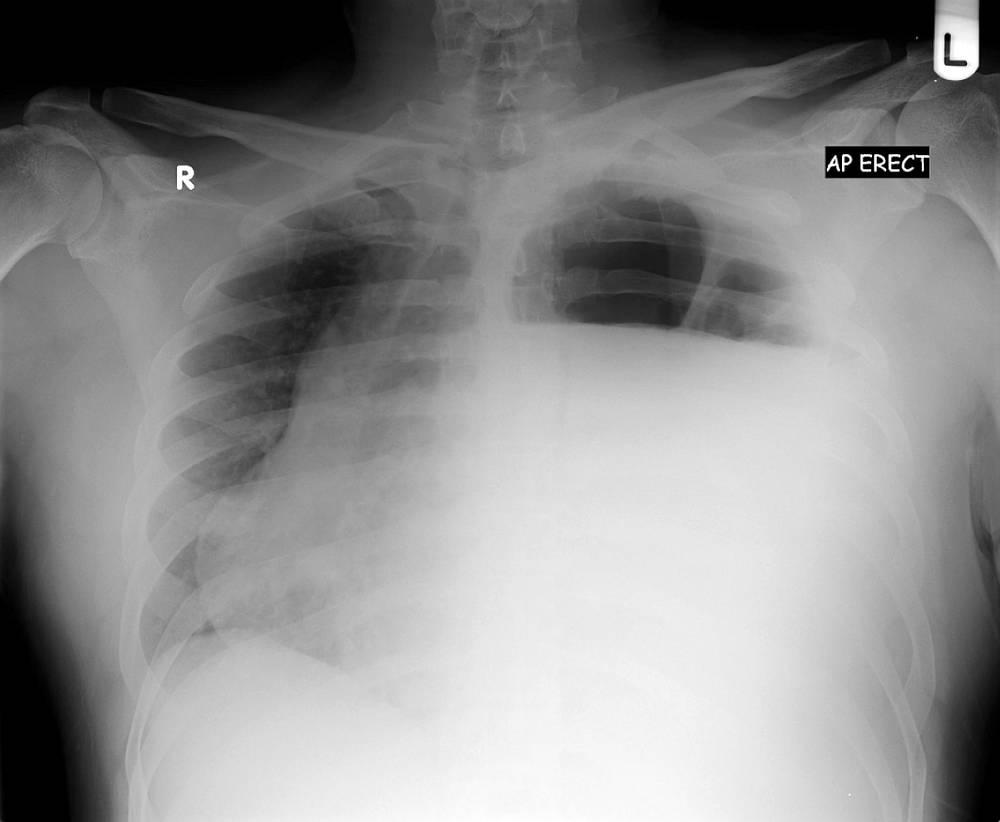

A 36 year old smoker was referred to a chest clinic following an employment medical. He had restrictive spirometry and a subsequent chest radiograph. His only complaint was of mild exertional dyspnoea.

Past medical history included Ramstedt pyloromyotomy for pyloric stenosis as a neonate and a road traffic accident (RTA) aged 16 sustaining left sided rib and pelvic fractures. The patient was a competitive full contact kick boxer from his early teens, training with weightlifting and admitted illicit anabolic steroid use.

What could be the diagnosis ?